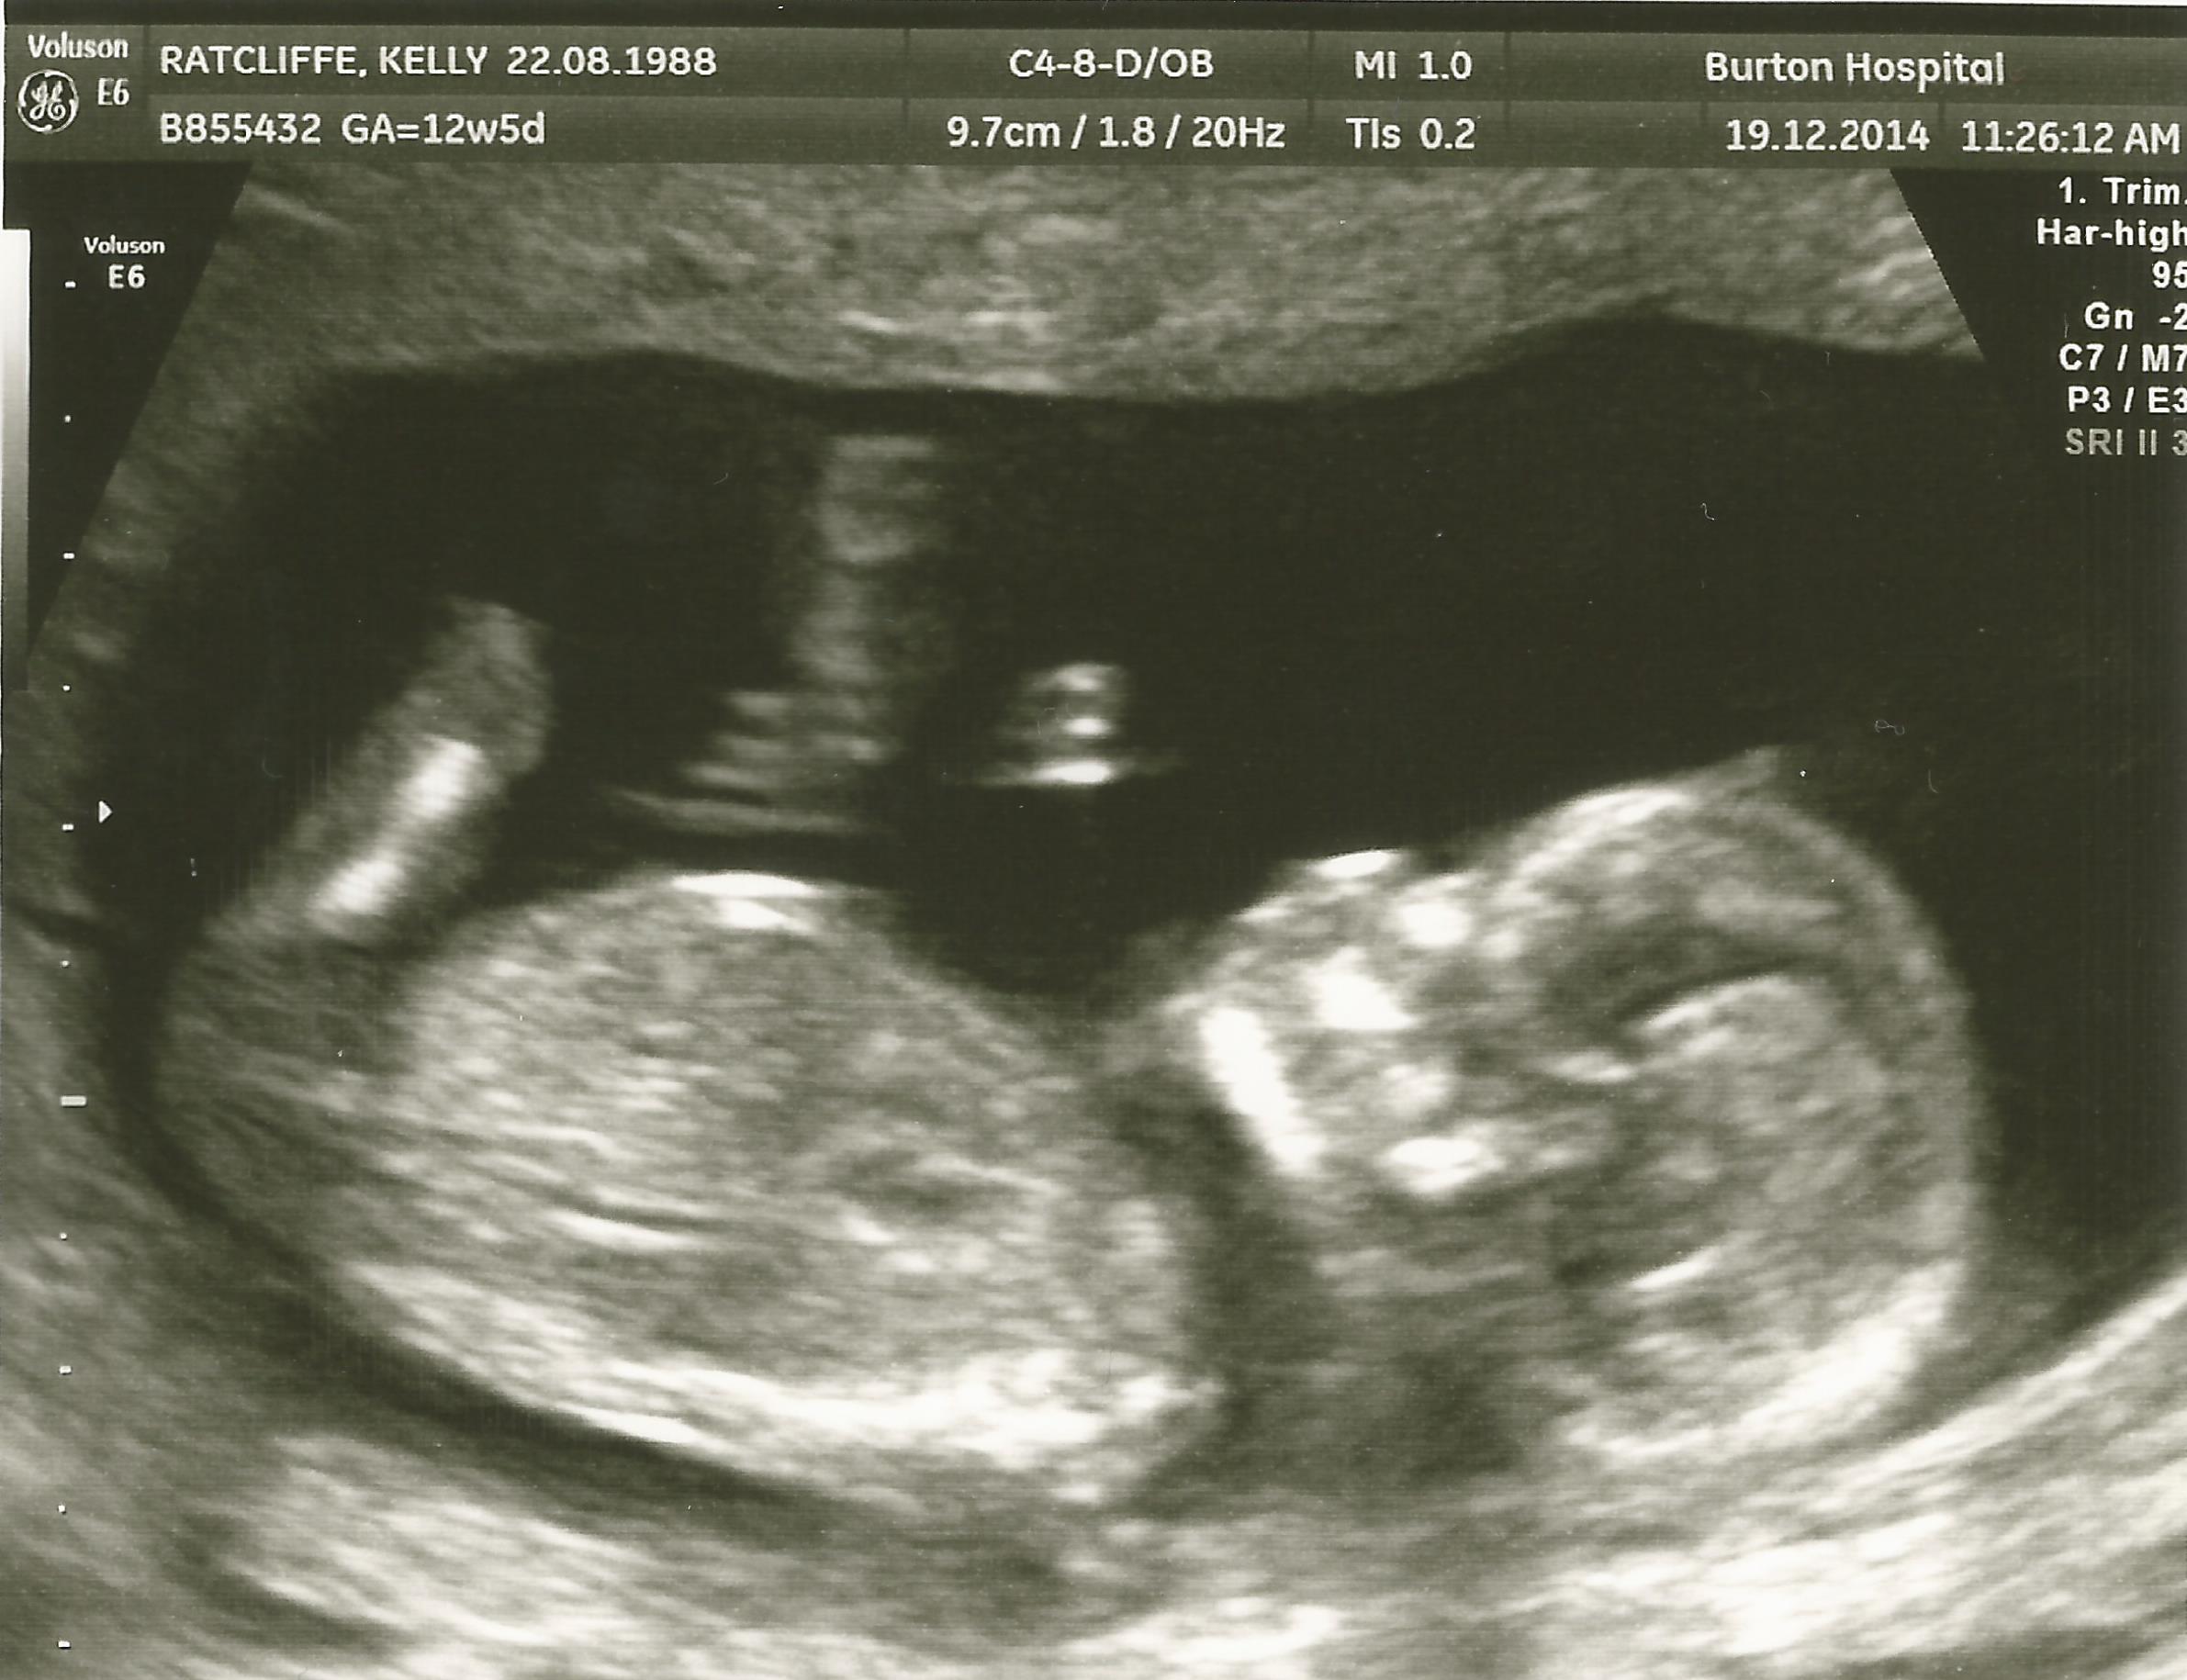

I'm not sure if a nub is even there im useless with things like this but im sure one of you lovely ladies can tell me :think:

I don't see a nub but very cute baby :)

Maybe girl

no nub but skull is girly :)

No nub

Agree no nub girly skull X

No clues, but very cute.

I give slight girl lean (but I am no expert at all!)

Girl guess from me